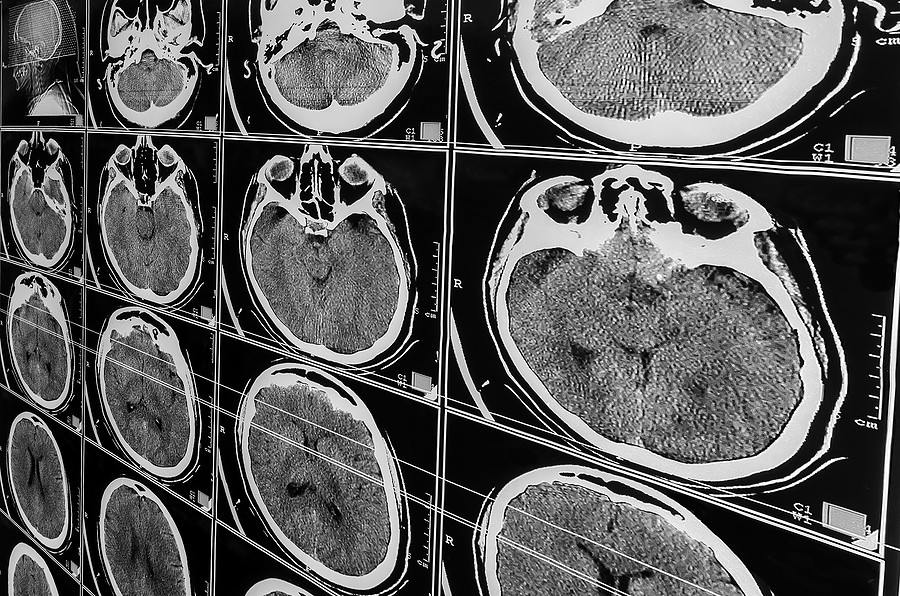

Insurance companies routinely challenge traumatic brain injury claims. These injuries are not always visible on CT scans or MRIs, particularly in the early stages. Adjusters may argue that your symptoms are subjective, exaggerated, or unrelated to the accident.